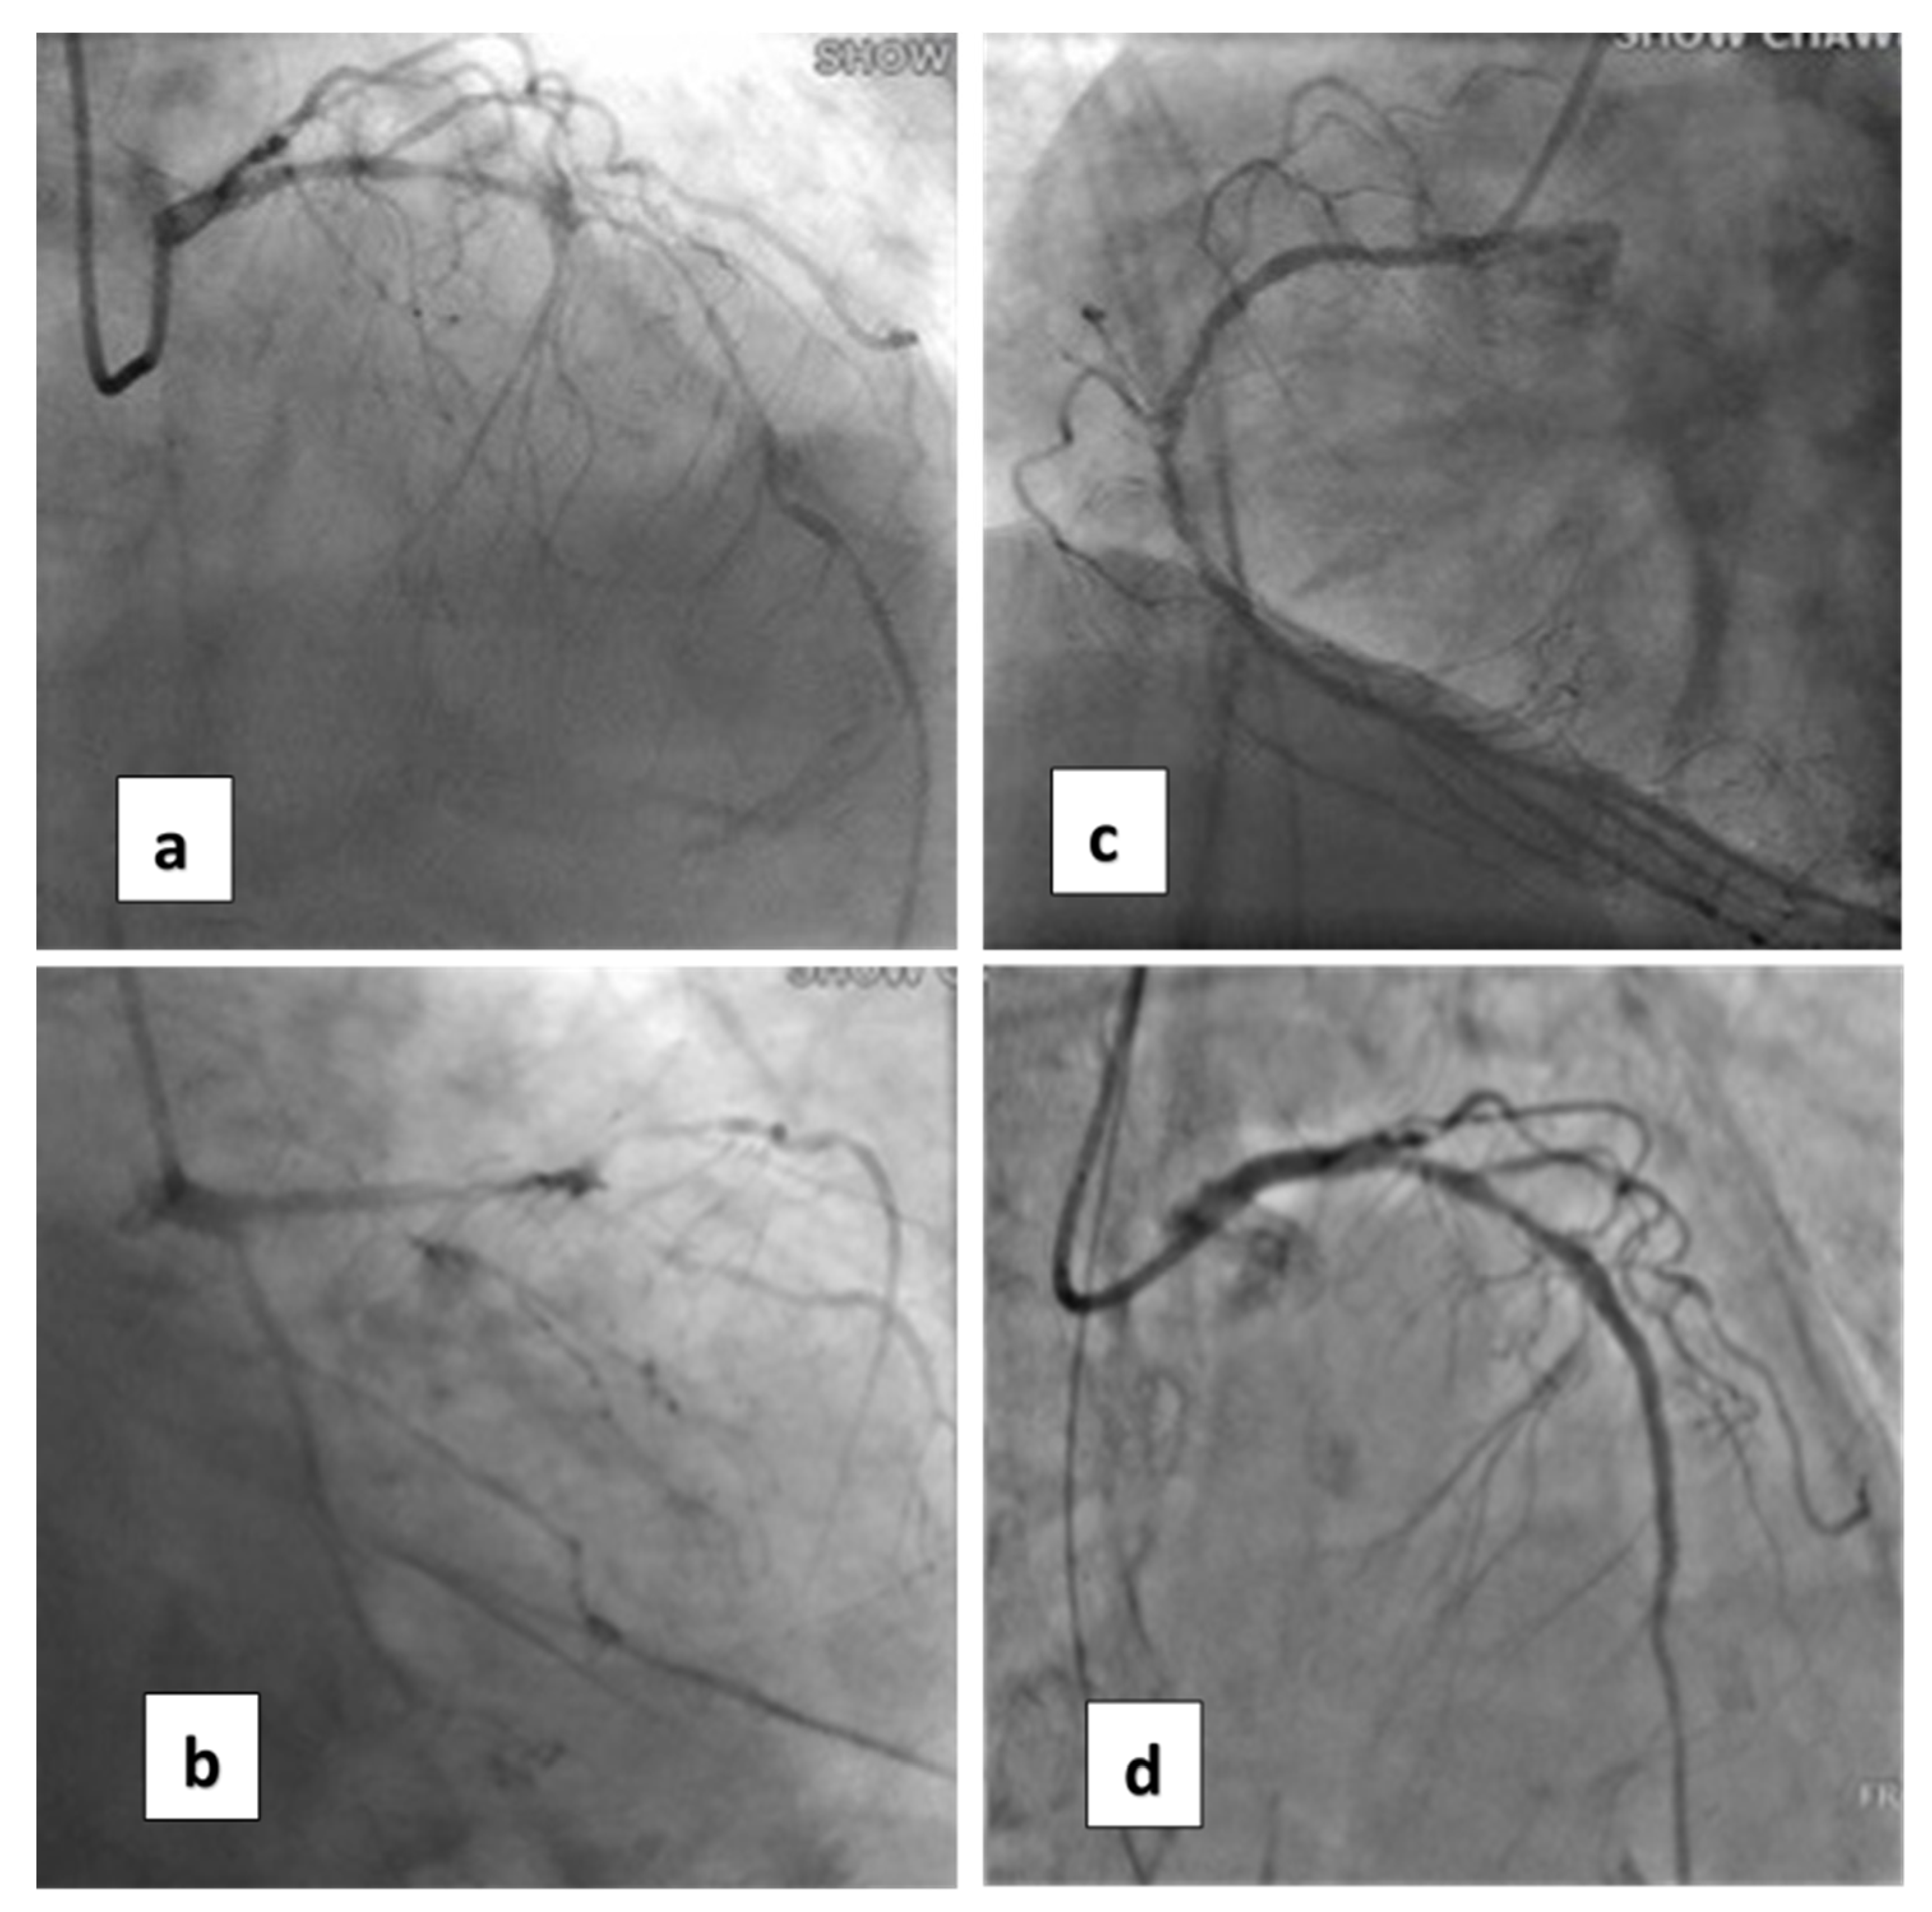

An 88-year-old female patient (height = 160 cm, body weight = 59 kg, BMI = 23) had increasing shortness of breath and visited our emergency department. Her past history included bronchial asthma and hypertension with regular treatment at our hospital. Initially, a mild elevated Troponin-I = 1.58 ng/mL (normal value, <0.16) was measured. Coronary angiography revealed three-vessel-disease: left anterior descending artery (LAD), middle-segment with long lesion up to 90% stenosis; left circumflex artery (LCX), distal-segment with chronic total occlusion; and right coronary artery (RCA), middle-segment with 40% tandem lesions (Figure 1a–c). Critical aortic valve stenosis (AS) with a mean pressure gradient (PG) of 43 mmHg was additionally diagnosed. The estimated aortic valve area (Gorlin equation) was 0.6 cm2. Her left-ventricular ejection fraction (LVEF) was about 58%.

Coronary artery bypass graft (CABG) and surgical aortic valve replacement (SAVR) or percutaneous coronary angioplasty (PCI) and TAVI were suggested to her family. They said they needed a family meeting to discuss it. However, the next day after the coronary angiogram, her dyspnea was more serious and her blood saturation of oxygen was down to 60%. So, she was intubated with mechanical ventilation. Based on her co-morbidities and old age, her logistic Euroscore was 25%, which is high risk (>13%). PCI and TAVI were preferred. PCI was performed next day of intubation, smoothly with two drug-eluting-stents (2.75 mm × 28 mm and 2.5 mm × 28 mm Xience, Abbott, Chicago, IL, USA) in the LAD (Figure 1d). The computed tomography (CT) showed moderate calcification of the aortic valve (Figure 2). Her family requested to wait for an important son coming back from abroad and for her to then receive TAVI. So, she was kept intubated with mild sedation. The patient’s renal function was within the normal limit: blood creatinine was 0.59 mg/dL (normal range 0.50–0.90 mg/dL) before PCI and 0.67 mg/dL after PCI; her hemodynamic condition was stable before and after stent implantation until the night prior to TAVI; four days after PCI, the patient’s vital signs became unstable. Atrial fibrillation (AF) with fluctuated ventricular response and arterial hypotension were noted. Inotropic agent (dopamine 8 μg/kg/min) was given. Upon arrival in the hybrid operation-room, tachycardia atrial fibrillation with about 110 beats per minute bpm was noted. After the induction of general anesthesia, her heart rate dropped to about 60 bpm and she subsequently went into cardiac arrest. Cardiopulmonary resuscitation (CPR) was therefore initiated for about 15 min. A veno-arterial (VA)-ECMO (Capiox, Terumo (Tokyo, Japan; with venous sheath 21 French and arterial sheath 16.5 French) was installed in her left femoral side. Ventricular tachycardia (VT) and ventricular fibrillation (VF) occurred, and 200 joule cardioversion was done twice to restore sinus rhythm. Urgent-TAVI was performed with a 25 mm × 4 cm ZMED2 balloon for pre-dilatation and a 31 mm CoreValve Evolut (Medtronic, Dublin, Ireland) implanted (Figure 3). After the TAVI procedure, she was transferred back to ICU. Despite the sinus rhythm being restored, her LVEF was 22%, which was due to cardiac arrest. We used Levosimendan-therapy and then her LVEF rose to 40%. Pulmonary hemorrhage occurred two days later on ECMO. Her activated partial thromboplastin time (APTT) reached 112.2 s (normal range 24.3–32.7 s). Heparin was held for hours and 10 units of packed red blood cells (RBC) and 4 units and fresh frozen plasma (FFP) were transfused. Then, her APTT was maintained between 50 and 60 s.

Figure 1. Coronary artery lesions of the patient. (a) Cranial view of coronary angiogram (CAG) revealed diffuse severe stenosis of the left anterior descending artery (LAD). (b) Caudal view of CAG shows total occlusion of the left circumflex artery (LCX). (c) CAG of the right coronary artery (RCA). (d) After percutaneous angioplasty (PCI) with two stents for LAD.